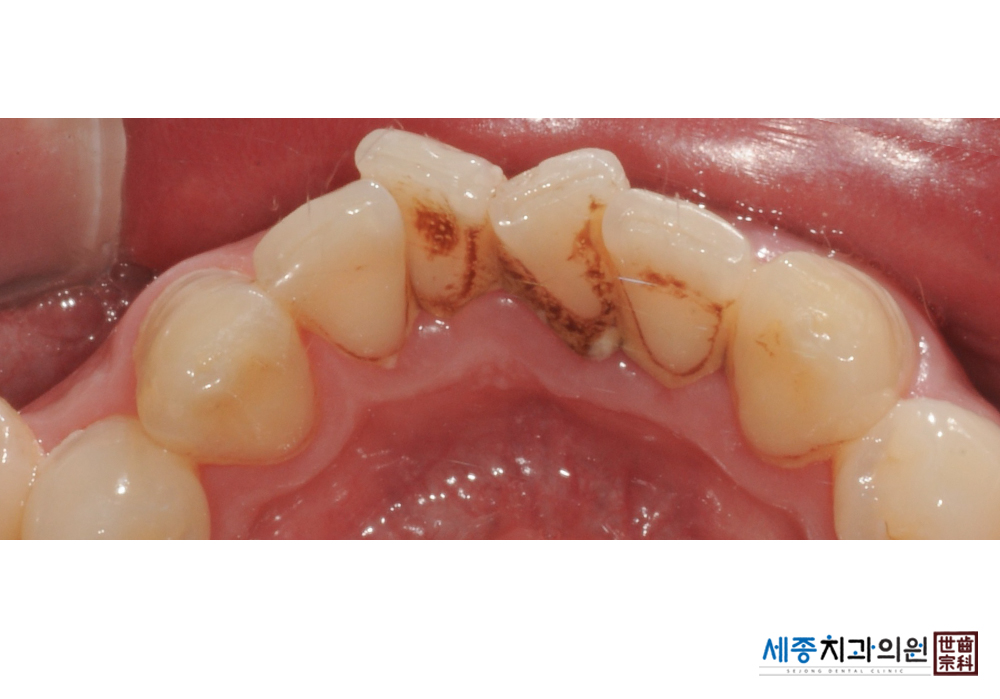

[스케일링] 치주질환 예방 스케일링 치료

치료전 : 2019-01-29

가글마취&저주파 스켈러를 사용한 스케일링